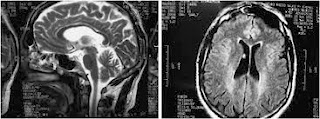

Hereditary Spastic Paraplegia